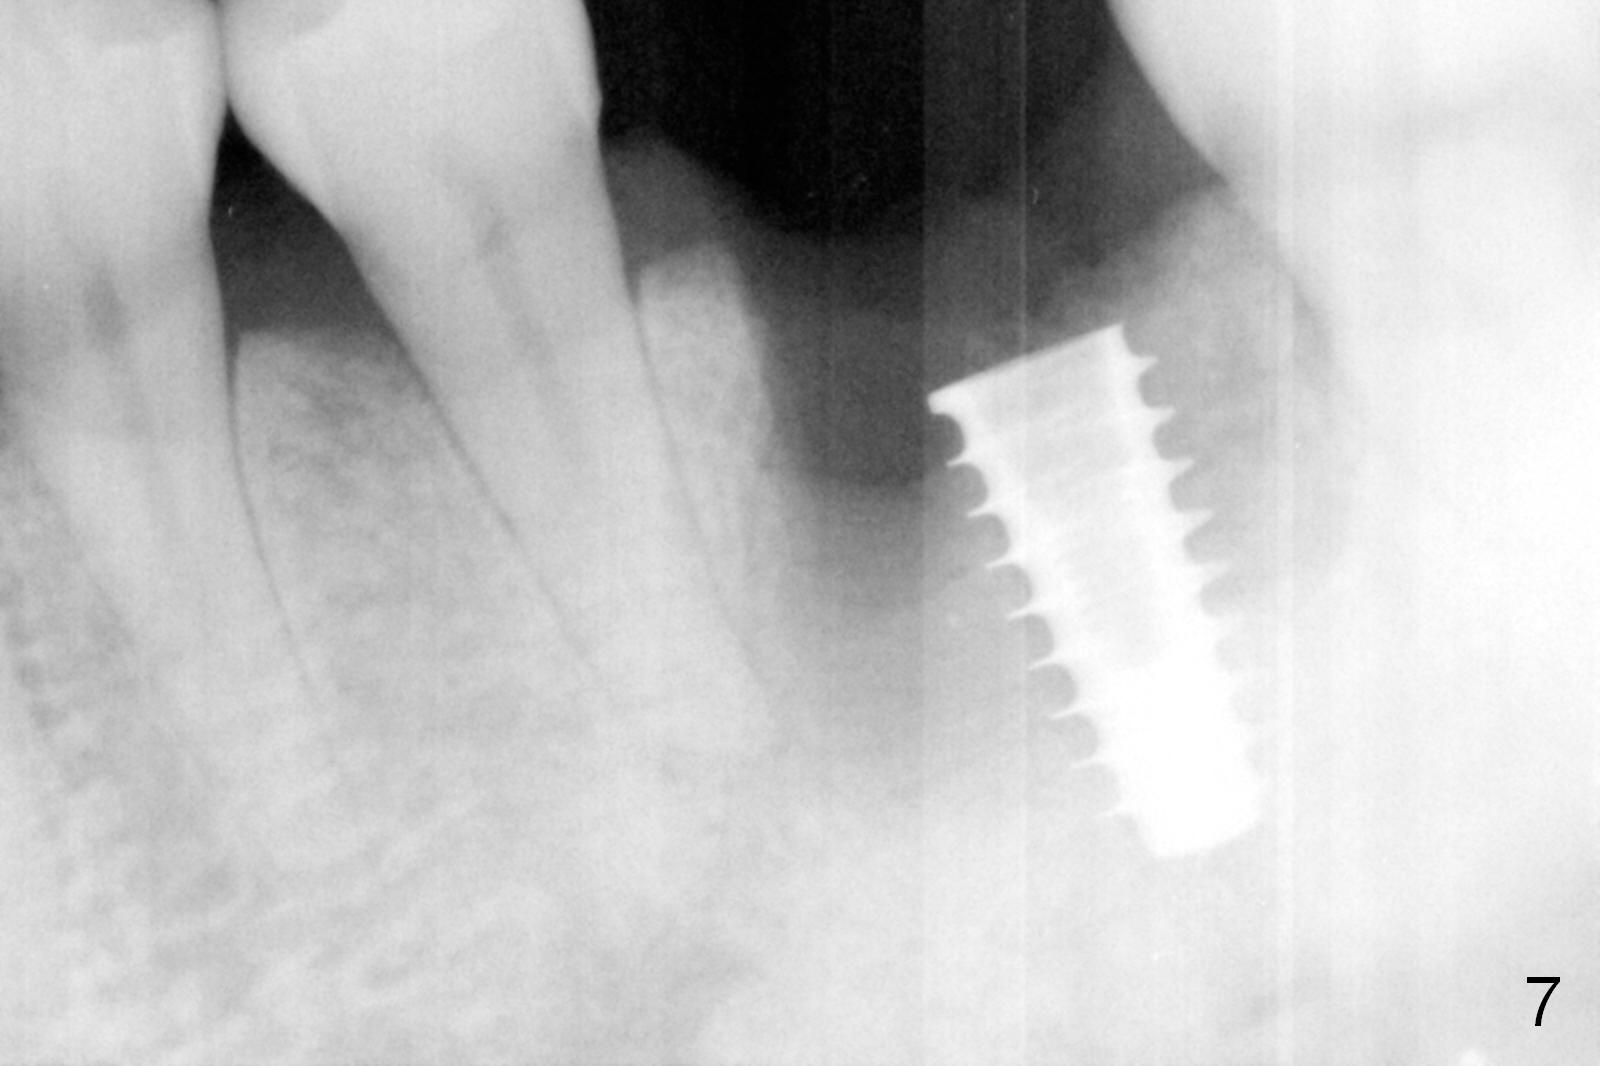

The asymptomatic tooth (#19) has a midbuccal fistula (Fig.1 <). The mesiobuccal pocket is 10 mm with purulent discharge from the sulcus (Fig.2,3). The mesiobuccal wall defect is confirmed when the tooth is extracted. Osteotomy is initiated lingually in the septum following septal crestoplasty (flattening) (Fig.4: using 1.6 mm drill for 9 mm). Since the lingual portion of the osteotomy is higher, it is difficult to use drill with stopper. For the narrow septum osteotomy, multiple drills are used sequentially (Fig.5 after 4.3 mm drill). A 4.5x11 mm dummy implant is placed (Fig.6) apparently too deep. When a 5x11 mm IBS implant is being placed, the depth is tightly controlled (Fig.7). The implant is apical to the lingual crest, whereas there is ~ 2 mm implant exposure buccally. That is, there is a large gap mesiobuccally (Fig.8), which is filled with .5-1.5 mm allograft (Fig.9 *). A 6.5x5.7(3) mm abutment (A) is placed and trimmed for an immediate provisional (Fig.10 P). The lacerated buccal gingiva is sutured as well as application of Perio Glue.